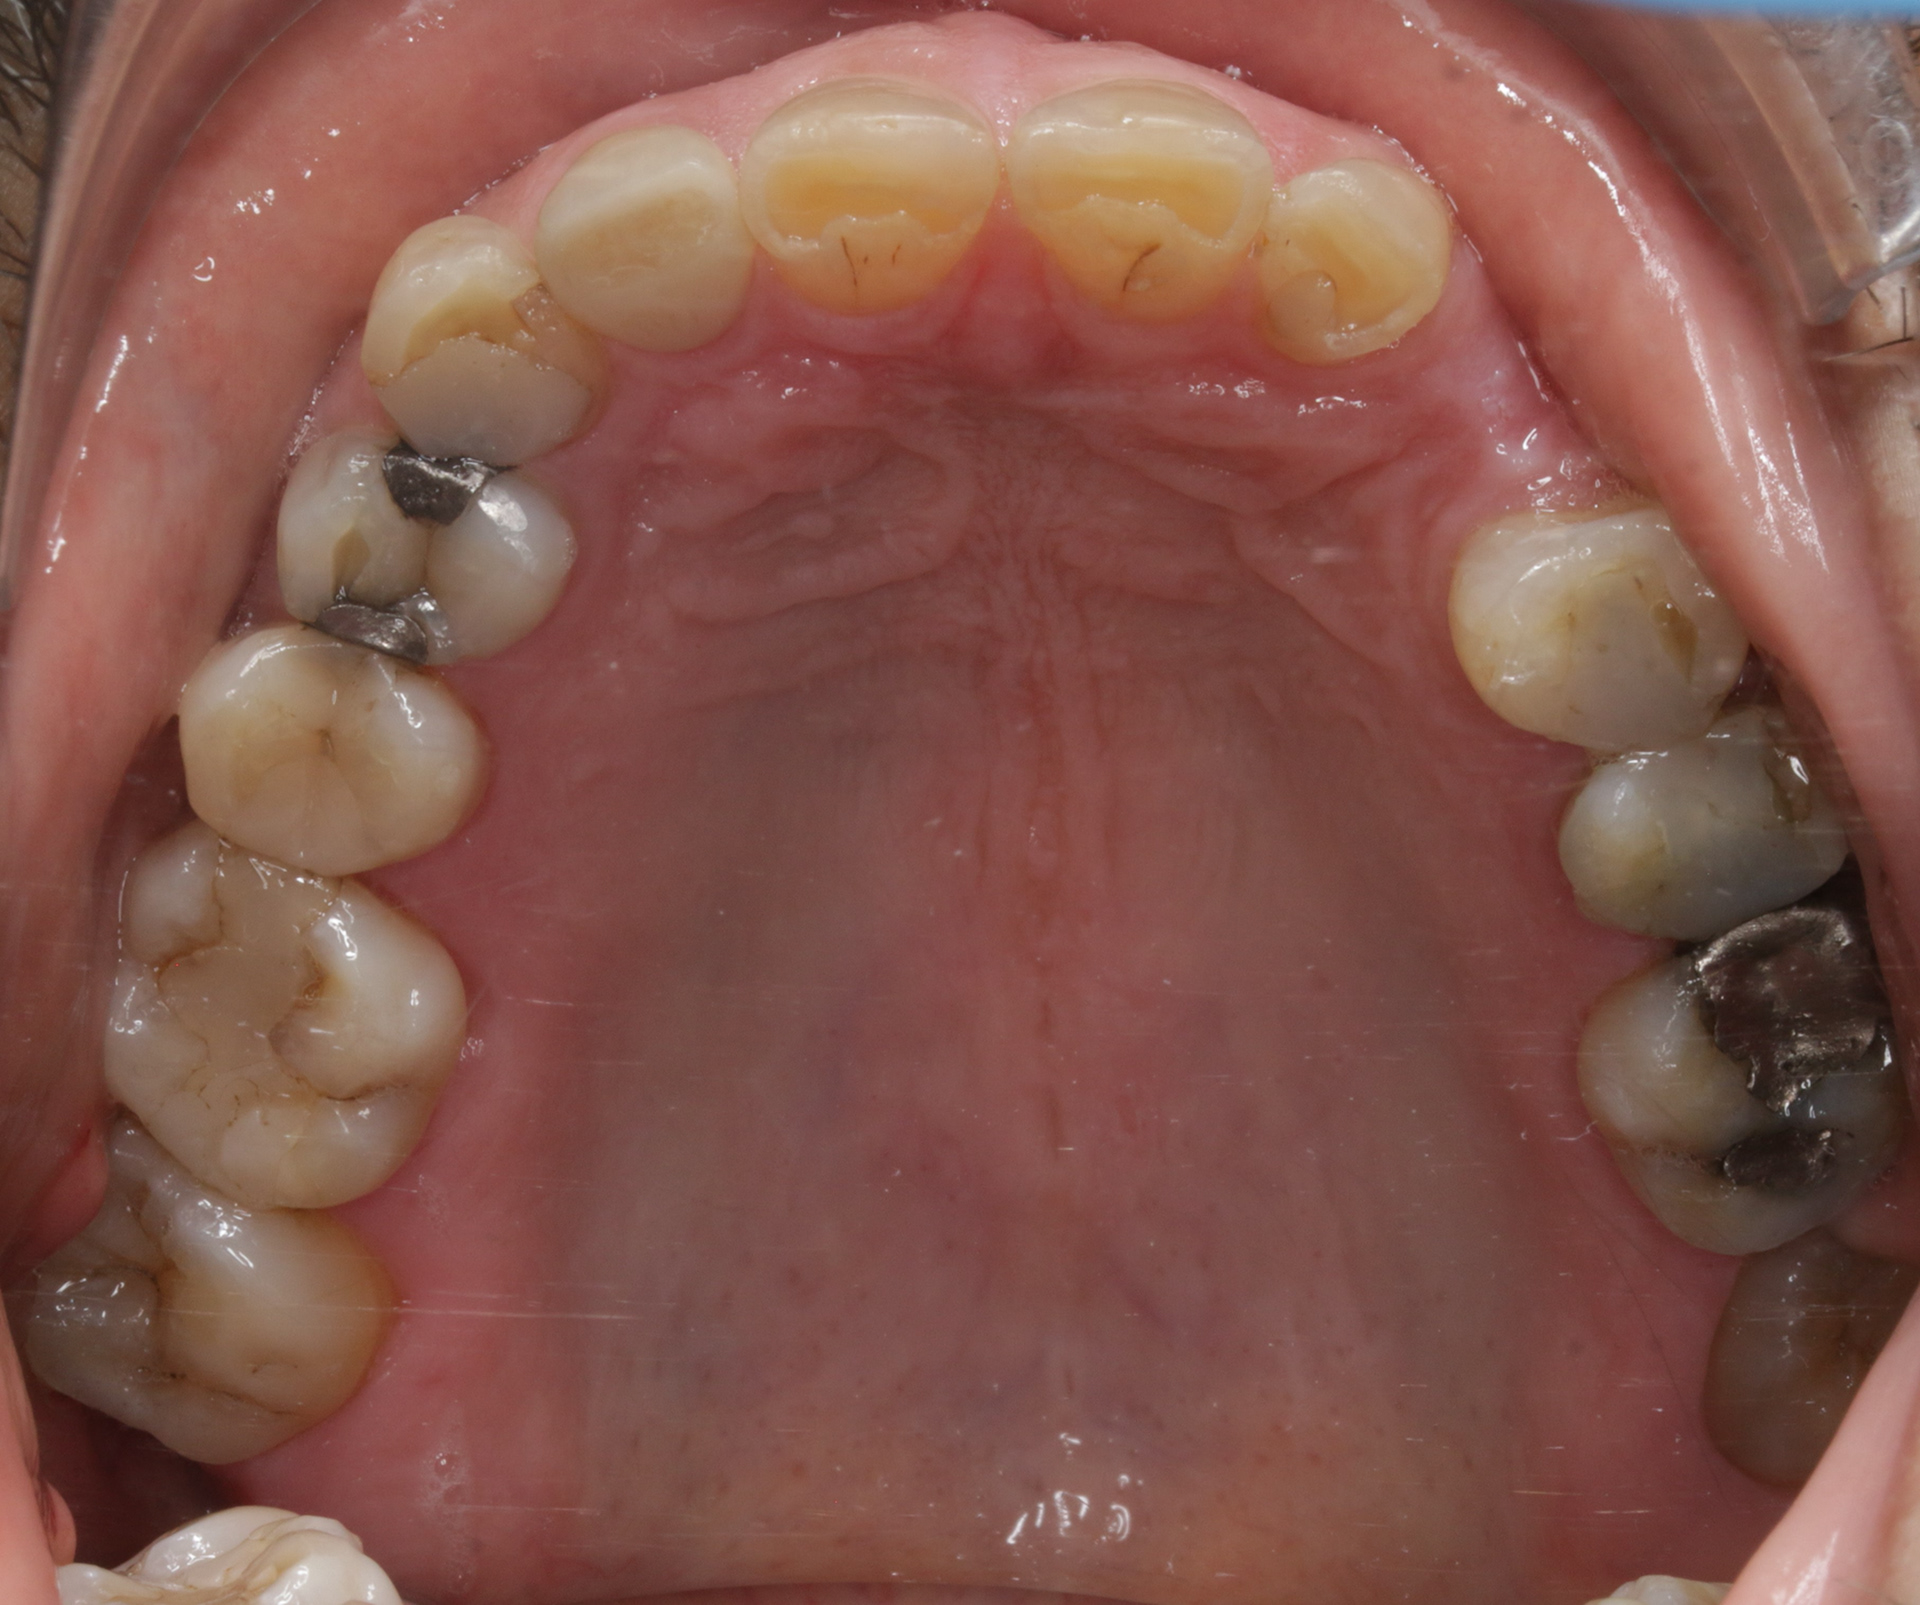

INITIAL RECORDS

BEFORE

BEFORE LEFT SIDE

BEFORE RIGHT SIDE